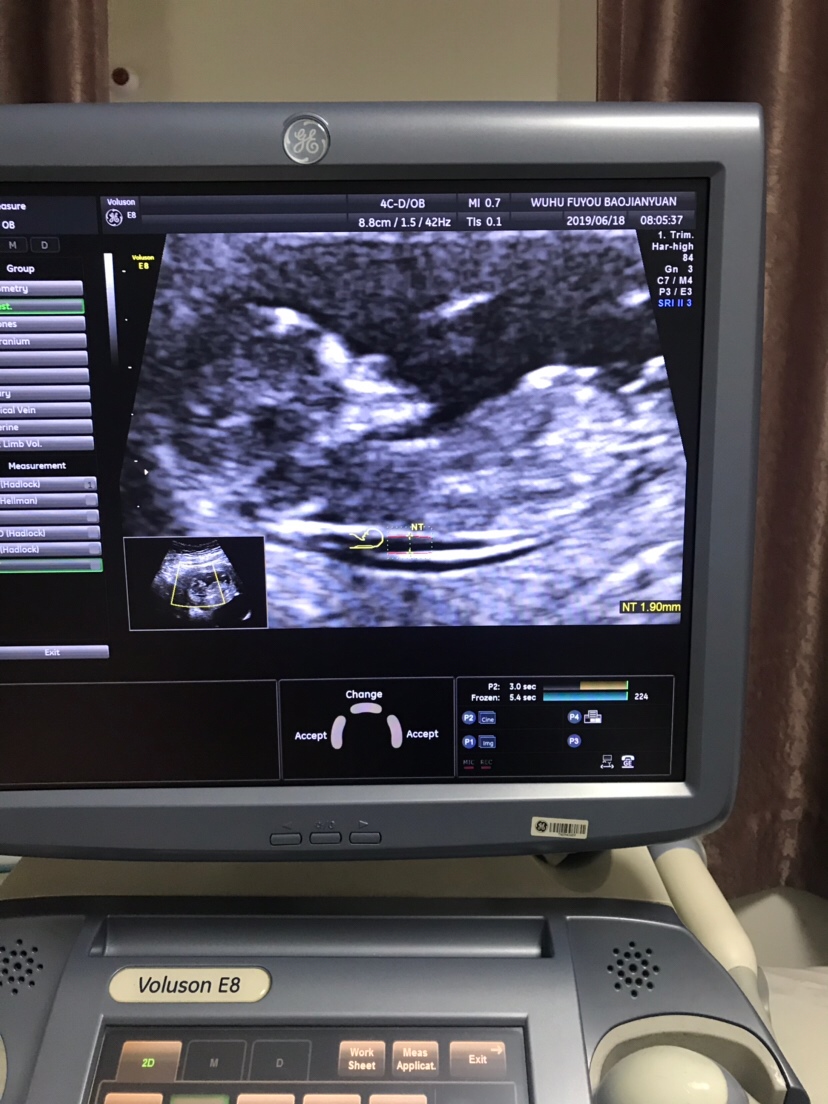

孕8周+3天